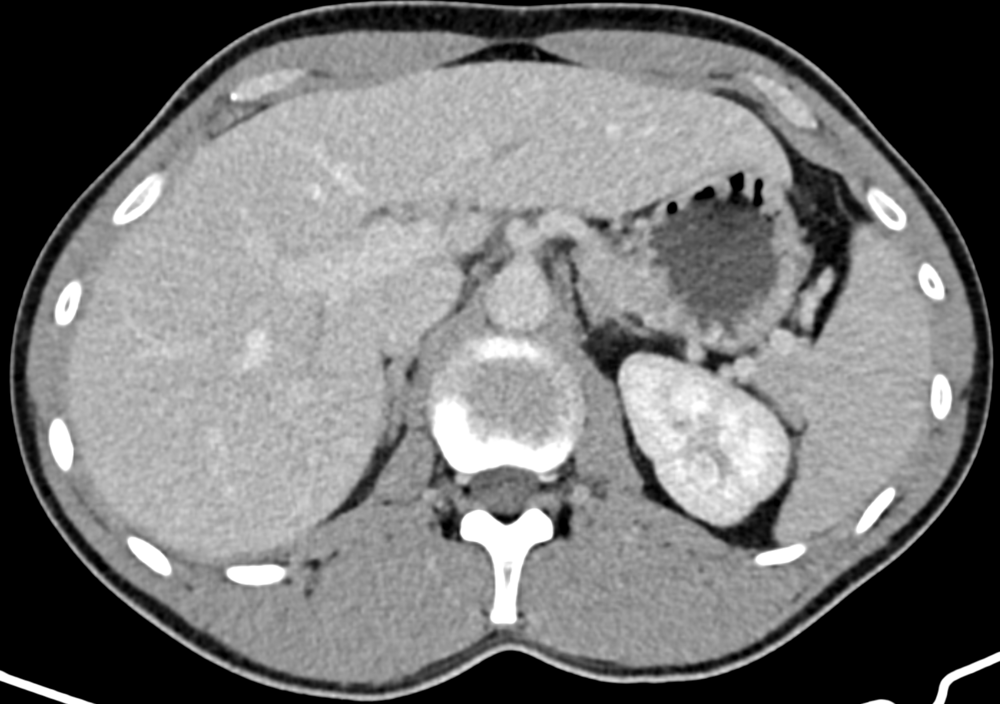

CT der Oberbauchorgane und des Magen-Darm-Traktes

Die Computertomographie (CT) der Oberbauchorgane und des Magen-Darm-Traktes zielt darauf ab, eine genaue Beurteilung von Organen wie der Leber, der Milz, der Bauchspeicheldrüse, der Gallenblase, des Magen-Darm-Traktes und der umgebenden Gefäße durchzuführen. Sie ermöglicht die Identifikation von Erkrankungen, Tumoren, Entzündungen oder anderen Anomalien in diesen Bereichen. Damit ist die CT ein wertvolles Instrument für die Diagnose von Erkrankungen der Leber- und Gallenwege, Pankreatitis, Tumoren, Divertikulitis und Darmverschluss. Die CT-Untersuchung des Bauchraumes ist im Vergleich zur MRT sehr schnell und dabei besonders für Patientinnen und Patienten geeignet, die schwer oder nur kurz die Luft anhalten können. Je nach klinischer Indikation entscheiden wir, ob die Anwendung eines Kontrastmittels erforderlich ist, um bestimmte Gewebe besser sichtbar zu machen. Die genauen Informationen aus dieser Untersuchung helfen Ihrem Arzt bei der Festlegung der Behandlungsstrategie.